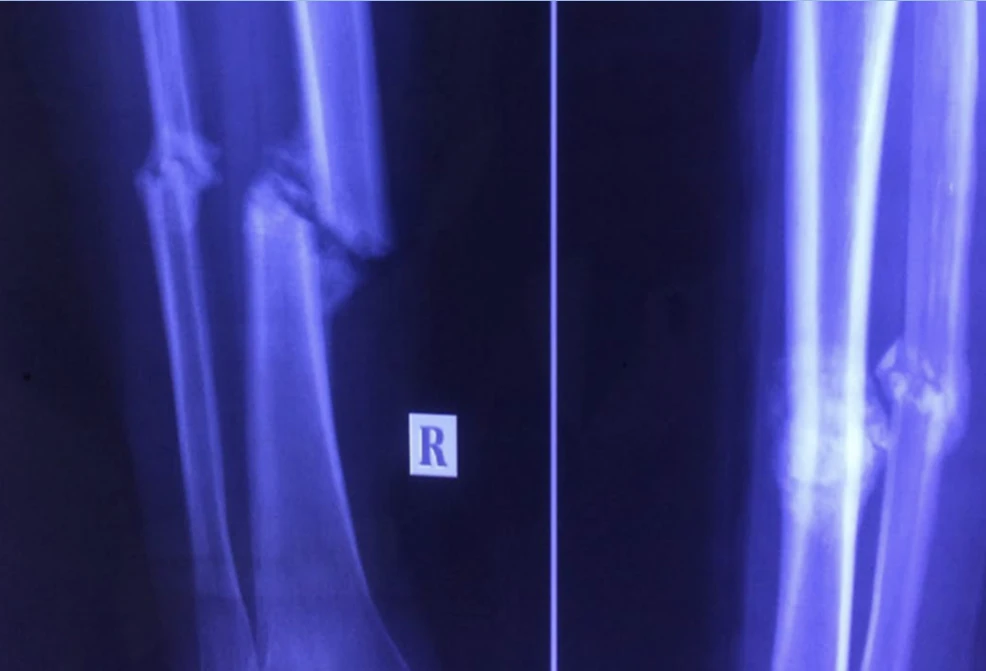

Trước đó, BV quận 11 tiếp nhận bệnh nhân trong tình trạng đau cẳng chân bên phải, không đi lại được. Sau khi thăm khám và thực hiện các xét nghiệm cận lâm sàng cần thiết, BV chẩn đoán bệnh nhân bị gãy xương, can lệch 1/3 giữa hai xương cẳng chân phải. Ngoài ra, bệnh nhân còn bị suy tim độ 3.

Chân phải bệnh nhân trước và sau khi phẫu thuật. Ảnh: CTV

Nhận định đây là trường hợp phức tạp vì xương cẳng chân gãy trên cơ địa người bệnh bị suy tim độ 3 nên BV quận 11 dự kiến các tình huống xấu có thể xảy ra trong quá trình phẫu thuật kết hợp xương. BV đã mời các chuyên gia về tim mạch của BV ĐH Y Dược TP.HCM hỗ trợ. Bệnh nhân đã được kết nối xương gãy thành công, sau khi lành hẳn sẽ đi lại được bình thường, không còn đau đớn.